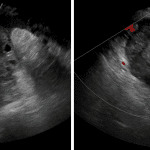

- 6 x 5.5 x 6.5 cm right adnexal structure with a thick hyperdense rim containing scattered hypodense foci and a hypodense center

- Ovarian torsion

Right adnexal structure which is favored to represent an enlarged ovary with a rim of hemorrhage, which can be seen with ovarian torsion. Recommend urgent pelvic ultrasound for further evaluation.